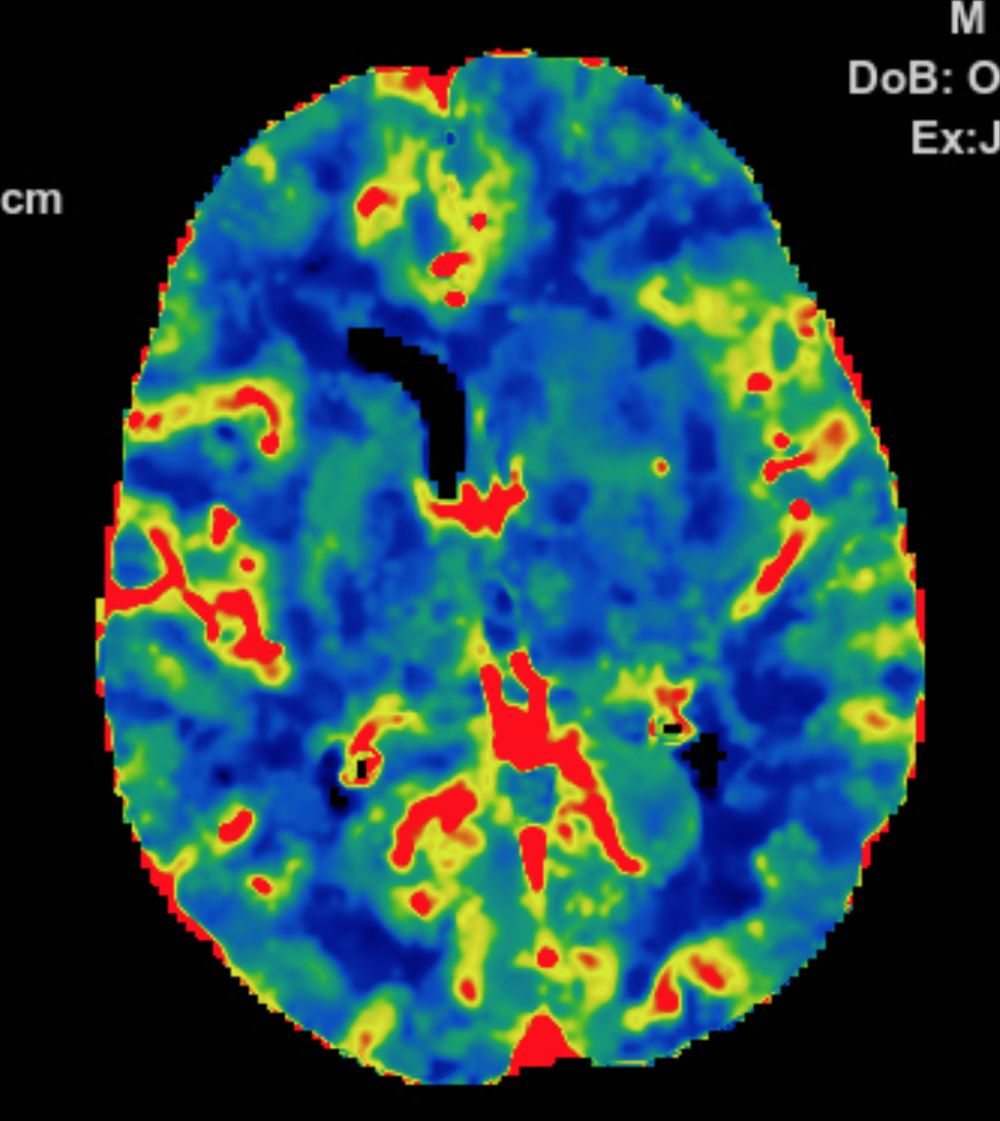

多模式CT影像提示:左侧大脑中动脉M1段闭塞,存在CBF-CBV不匹配。

图3 CTP存在CBF-CBV不匹配

2.手术指征:患者应用阿替普酶溶栓后症状仍持续加重,CTA示左侧大脑中动脉闭塞。CTP存在CBF-CBV不匹配,有介入治疗指征。